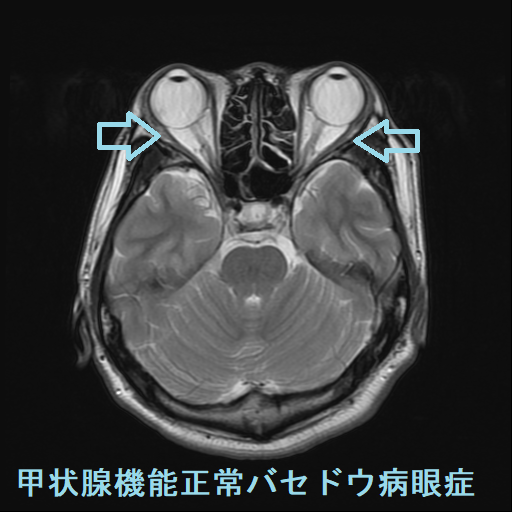

甲状腺ホルモンが正常なのに進行するバセドウ病眼症があります(甲状腺機能正常バセドウ病眼症)。

甲状腺機能正常バセドウ病眼症は、

- 片眼性が多いとされるが、両眼性のことも

- 活動性は低いとされるが、高活動性のことも

- TSAb 弱陽性。TSAbが正常上限値(110%未満が正常なので、100-109%)の事は多いが、強陽性のことも(下記)

- TRAb(通常のバセドウ病抗体)は陰性が多い(下記)

- 甲状腺腫は認めない事が多い